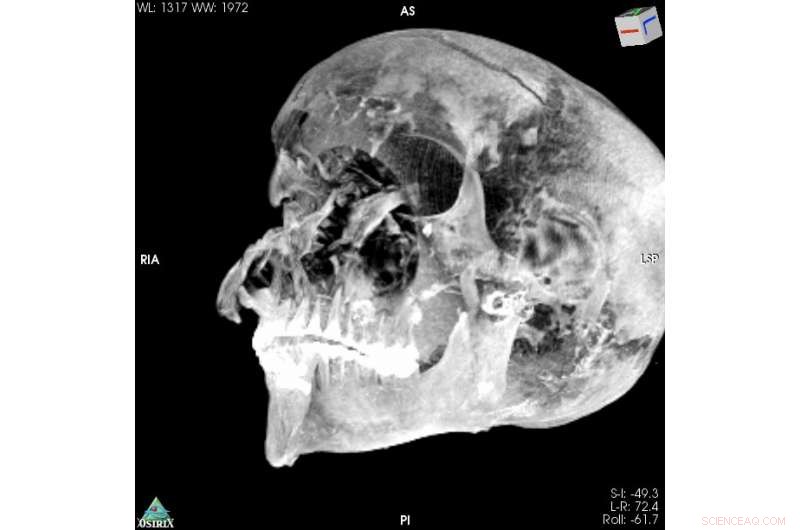

3D Virtual Reality image of the pharaoh's skull. Credit: Sahar Saleem

The CT study also determined that Seqenenre was about 40 when he died, based on the detailed morphology revealed in the images, providing the most precise estimate to date.

But computed tomography (CT) scans of the mummified remains of Seqenenre revealed new details about his head injuries, including previously undetected lesions that embalmers had skillfully concealed.

For example, the CT scans, combined with other evidence, suggest the execution had been carried out by multiple attackers, which the scientists confirmed by studying five different Hyksos weapons that matched the king's wounds.